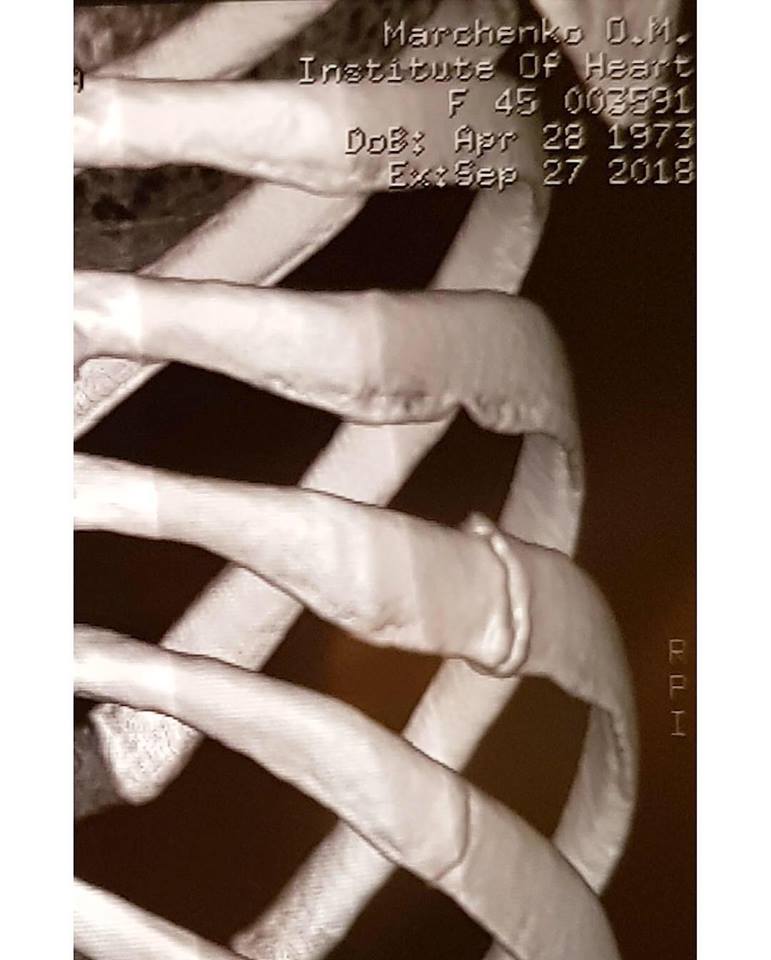

К посту Оксана Марченко приложила флюорографию ребер и медицинские справки, подтверждающие перелом двух ребер. А также фото с Дмитрием Чаплиным.

"Во время подготовки к прямым эфирам, на репетиции, я сломала два ребра. Это была очень острая боль, но я подумала, что сильно потянула связки или мышцы, принимала обезболивающее и, сцепив зубы, продолжала репетировать. Временами боль была нестерпимой, я шла в раздевалку, плакала, чтобы никто не видел, ставила себе еще более сильные обезболивающие инъекции и снова репетировала", - написала Оксана Марченко, отметив, что участие в шоу было очень важно для нее, поскольку это мечта ее дочери.

"Перед эфирами все повторялось: болеутоляющие - и я снова могла танцевать и работать. Сегодня мне не больно, но из-за усложняющейся программы врачи опасаются рецедивов, ведь ткани в местах переломов еще достаточно слабые. А я не могу и не хочу работать вполсилы. До последнего времени об этой истории никто не знал, но сегодня я хочу быть искренней. Я победила свою боль, свои страхи и неуверенность. Мною гордится моя семья, мои родители, друзья, и я от всего сердца хочу их поблагодарить за поддержку и любовь", - написала телеведущая.